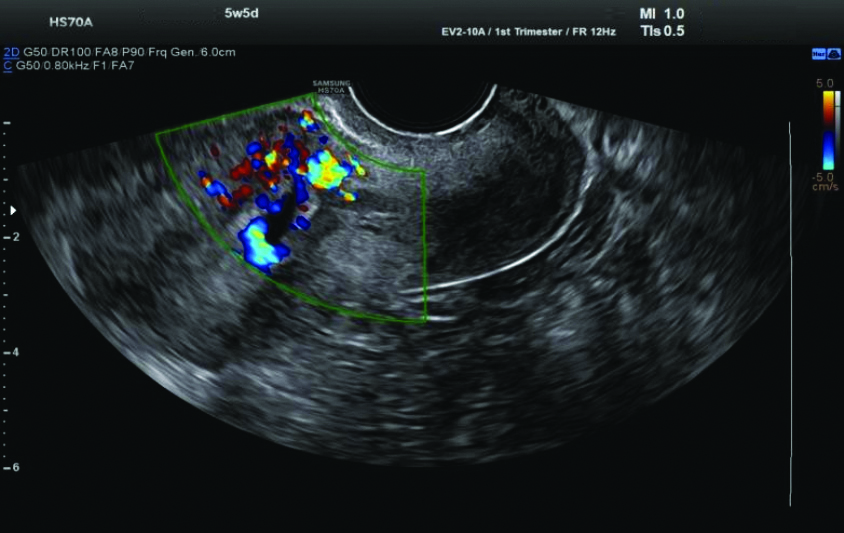

Ultrasound (USG) examination: The USG revealed a single gestational sac in the lower uterine segment at the region of the previous caesarean scar, extending into the anterior myometrial wall with surrounding increased vascularity and decidual reaction, suggestive of scar ectopic pregnancy. The foetal pole and yolk sac were not visualised. The mean gestational sac measured 9.9 mm, corresponding to 5.5 weeks [Table/Fig-4,5].

Ultrasound (USG) revealed a single gestational sac in the lower uterine segment.

Increased vascularity and decidual reaction on Ultrasound (USG).